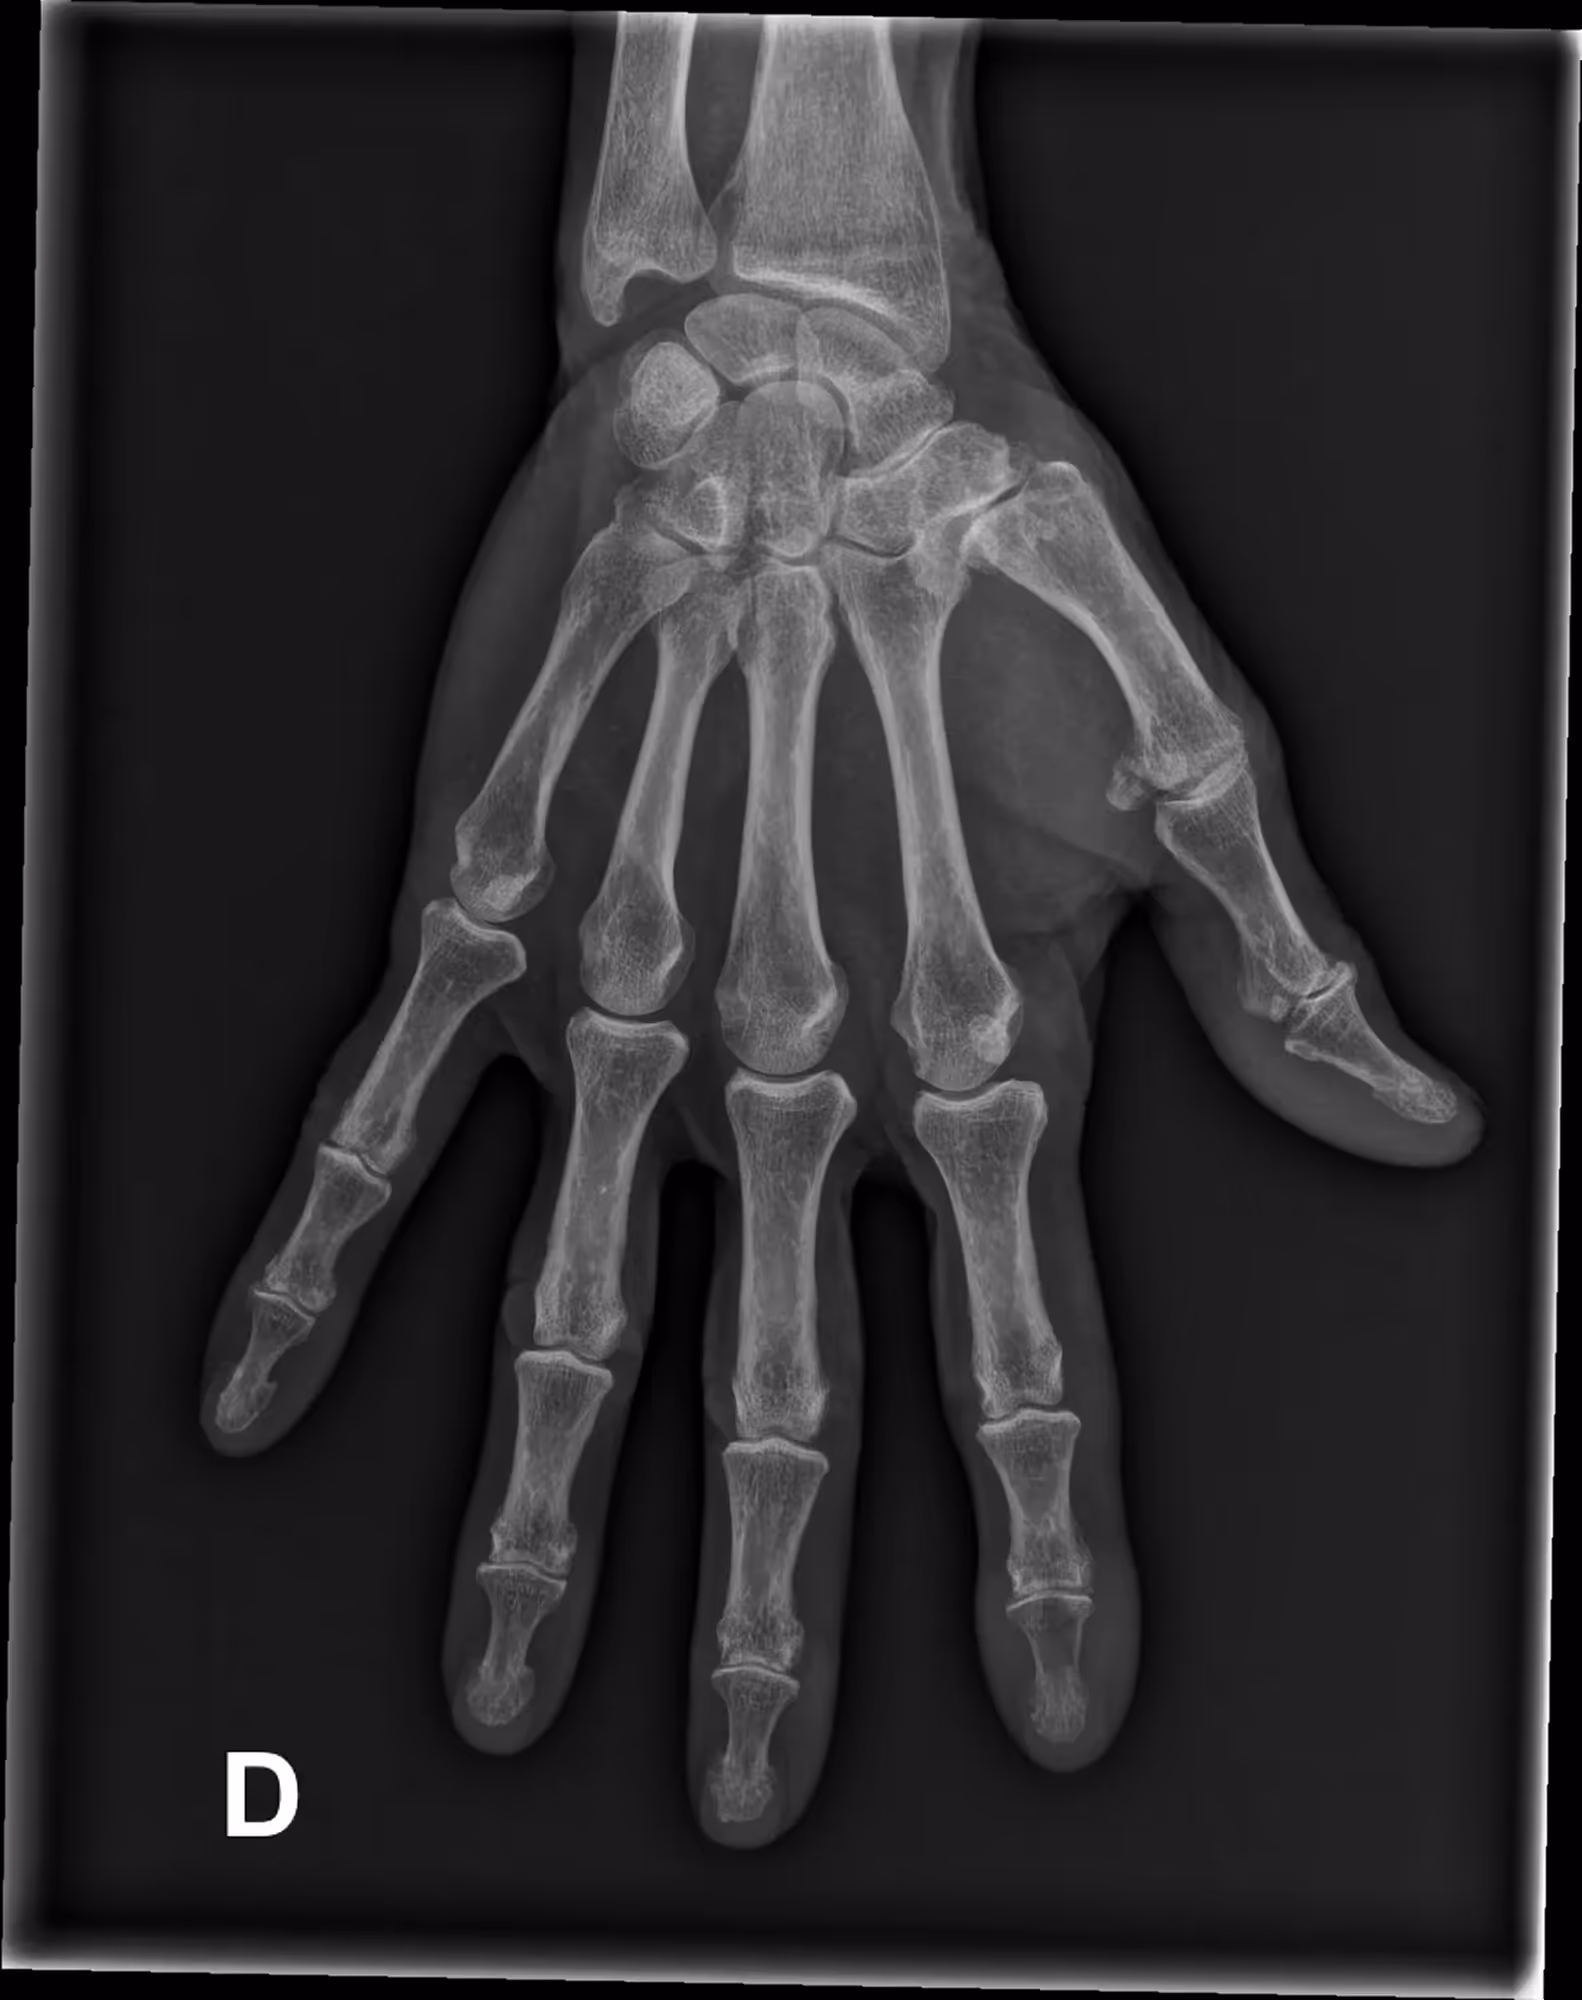

A 79-year-old female was bitten by her dog and consulted three weeks later due to lingering pain.

Results

BoneView detected a lesion of the first phalanx, revealing infectious osteitis.